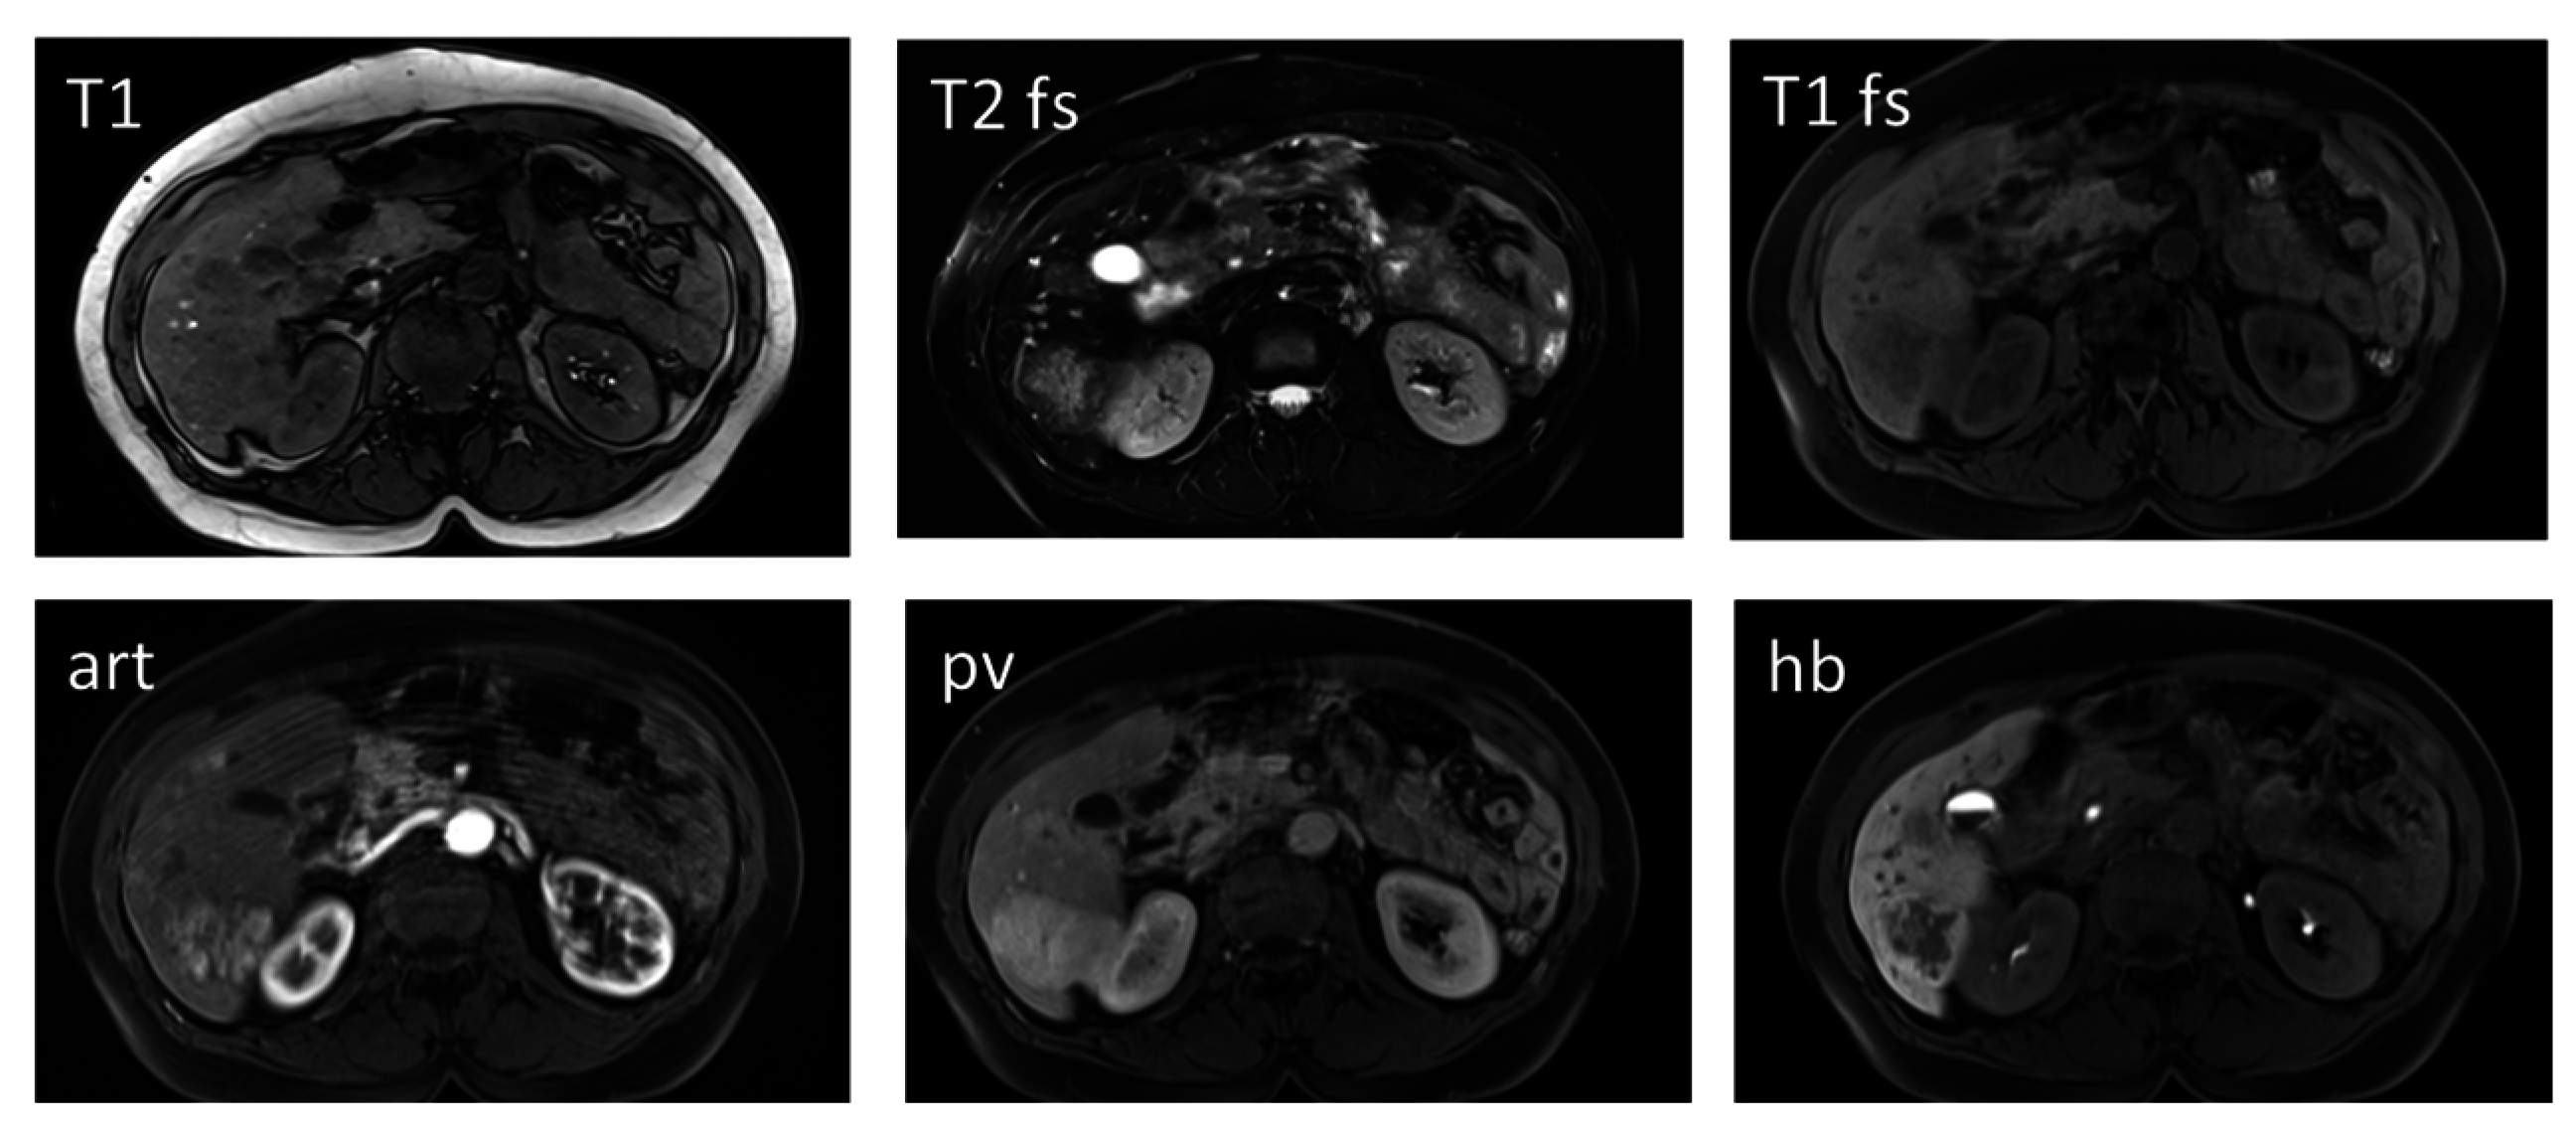

Haemangioma as the most common benign liver tumor is considered to be a developmental malformation that is generally without clinical significance [26]. It is usually hyperechogenic in US, although this is not a specific finding for diagnosis. Dynamic CT and MRI with extracellular contrast media showing the classical fill-in contrast behavior are useful for the diagnosis. However, care should be taken when hepatocyte-specific contrast agents are administered, in order to evaluate hepatic nodules. One needs to be aware that haemangiomas do not show the typical prolonged enhancement in the portal venous and hepatobiliary phase after Gd-EOB-DTPA (Figure 3). This is due to the fact that Gd-EOB-DTPA shows much faster wash-out from the blood pool than do iodine-based contrast agents and Gd-DTPA [26]. Thus, diagnostic confidence for haemangiomas can be improved when considering the T2-weighted images in which typical haemangiomas usually show homogeneous bright signal intensity.

Figure 3. A 47-year old female patient with a large haemangioma in the left liver lobe. Typical image series obtained using hepatocyte specific contrast media is shown. A large lesion is visible in the left liver lobe which presents hypointense in T1, markedly hyperintense in T2 with bright signal in the ADC map. In the contrast-enhanced dynamic series performed after intravenous application of a liver specific contrast agent, the lesions shows centripetal enhancement. In the hepatobiliary phase obtained 20 min after contrast injection, the lesion is hypointense in contrast to the hyperintense liver parenchyma. Haemangiomas do not show the typical pooling appearance in the hepatobiliary phase. Diagnostic confidence can be increased when considering the typically bright signal in T2 and the high ADC values. T1: T1-weighted image; T2: T2-weighted image with fat saturation; ADC: apparent diffusion coefficient map; art: contrast-enhanced image in the arterial phase; pv: contrast-enhanced image in the portal venous phase; hb: contrast-enhanced image in the hepatobiliary phase.